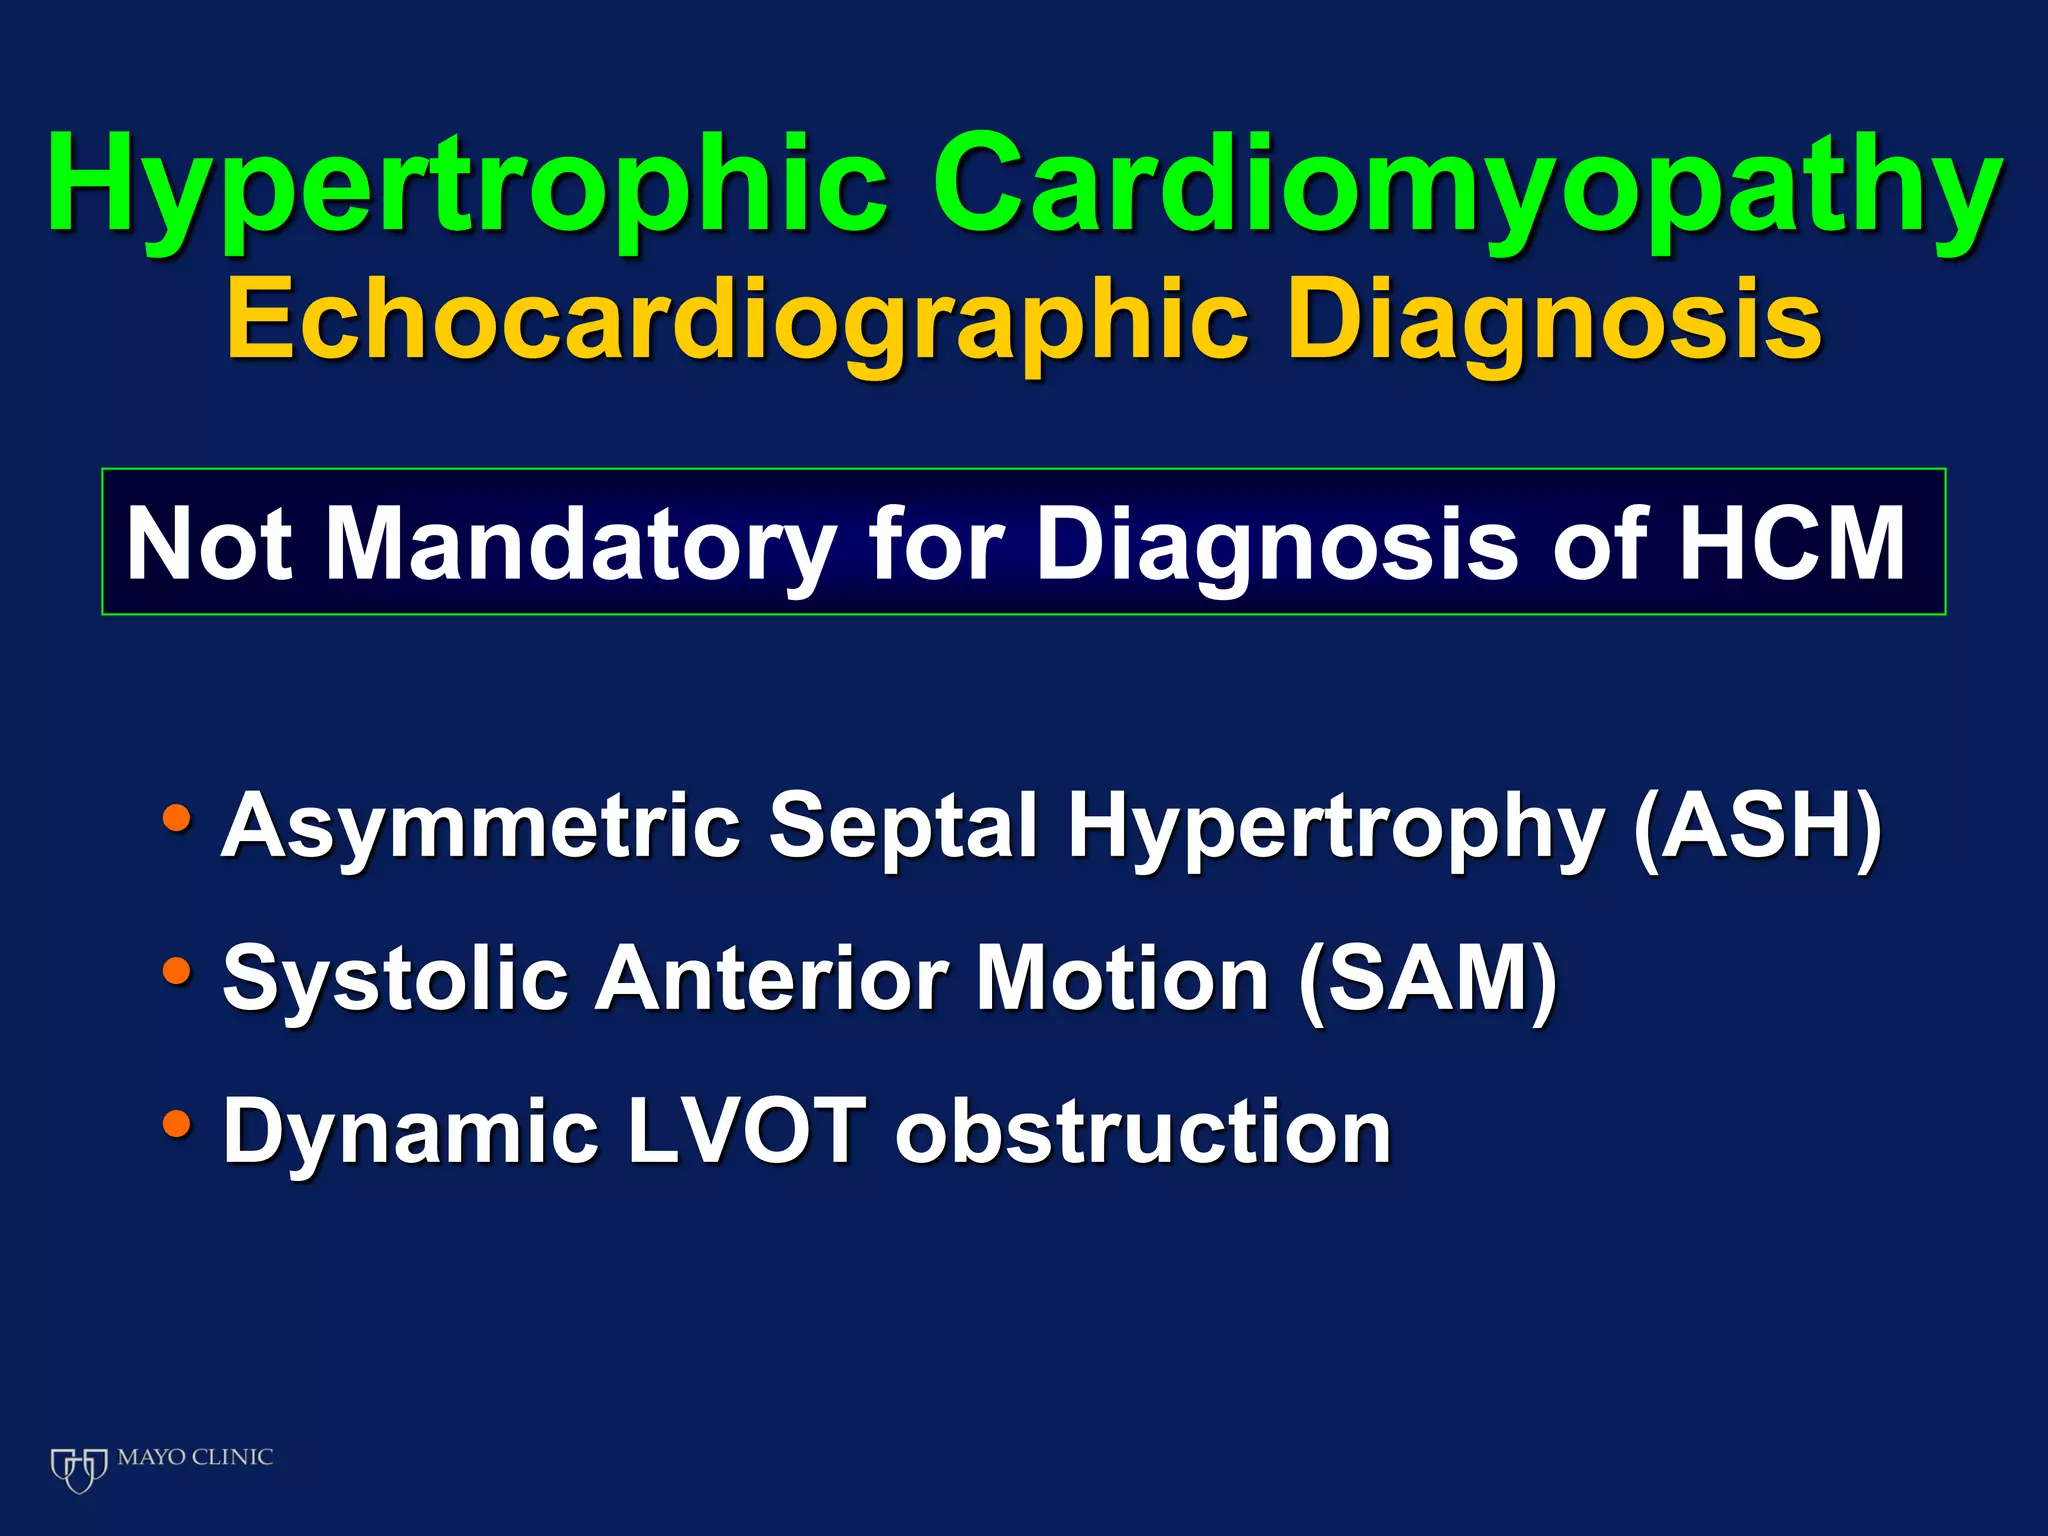

Echocardiography plays an essential role in diagnosing hypertrophic cardiomyopathy (HCM) by demonstrating left ventricular hypertrophy of 15mm or greater that is asymmetric and cannot be attributed to another cause. Echocardiography can also identify the characteristic patterns of hypertrophy such as sigmoid septum, reverse curvature of the septum, and apical hypertrophy. It is used to detect complications of HCM such as left ventricular outflow tract obstruction, mitral regurgitation, and apical aneurysms. Risk stratification for sudden cardiac death utilizes echocardiography to identify features such as massive hypertrophy, abnormal blood pressure response to exercise, and nonsustained ventricular tachycard